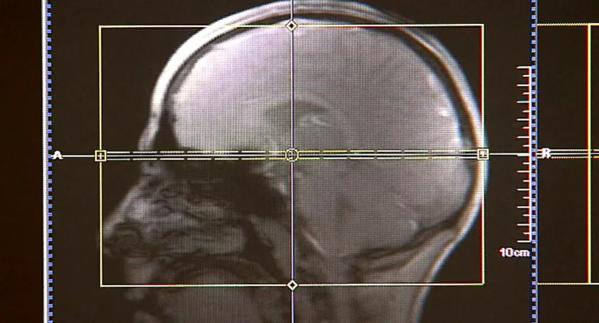

New Discovery Made in Research Diagnosing Impact-Related Brain Disease

New Cleveland Clinic research shows how a biomarker in the blood could possibly help with detecting CTE, a brain disease caused by repeated head impacts.

CLEVELAND – Cleveland Clinic researchers have made a new discovery that could be helpful when it comes to diagnosing CTE, which is a brain disease caused by repeated head impacts.

Currently, CTE can only be diagnosed after death, making it impossible to detect and treat.

His research shows that elevated levels of a certain biomarker in the blood correlates with a decline in cognitive function and structures of the brain.